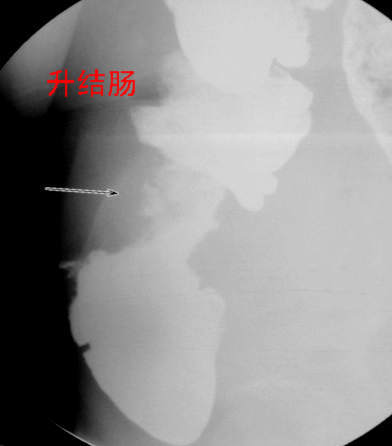

67岁女性,腹痛、腹胀半月余。查:右侧腹部有触痛,可触及肿物。

支持升结肠肿瘤性病变。

常规考虑---结肠癌,不排除诱发肠套叠了。

支持升结肠癌。

支持考虑升结肠癌。

谢谢大家讨论。与x6045完全不同。本例手术结果为右侧结肠旁沟及盆腔多发脓肿。术后病人恢复良好,现已出院。

手术见结肠旁沟及盆腔多发脓肿。

感谢楼主反馈结果!造影见果核征,首先考虑肿瘤,即使误诊也应该这样考虑。